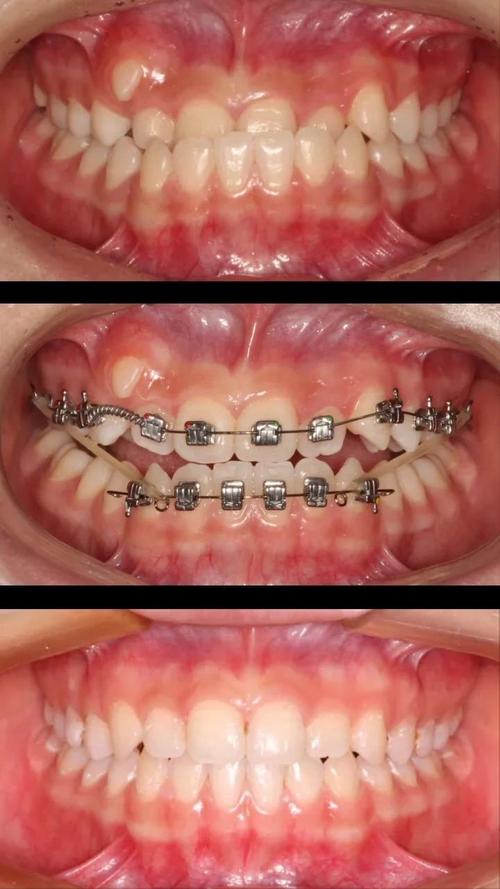

正畸片段弓是一种在口腔正畸治疗中针对局部牙齿问题进行精准矫治的技术,其核心在于通过设计特定的弓丝片段(而非全口弓丝),对目标牙齿施加生物力学力,实现牙齿的位置、角度或咬合关系的调整,与传统全口矫治不同,片段弓更聚焦于“局部干预”,适用于仅需少数牙齿移动的病例,既能简化治疗流程,又能减少对非目标牙齿的干扰,因此在临床中应用广泛。

正畸片段弓的治疗流程与操作要点

正畸片段弓的治疗需严格遵循“诊断-设计-实施-调整”的流程,具体步骤如下:

- 诊断与设计:通过口腔检查、X线片(如曲面断层片、头颅侧位片)、模型分析,明确目标牙齿的移动方向和幅度,设计片段弓的形态、材质(如不锈钢丝的强度高、镍钛丝的柔韧性好)和托槽位置(通常选用方丝弓托槽或直丝弓托槽,便于精细控制)。

- 弓丝弯制与试戴:根据设计图弯制片段弓,临床试戴时检查弓丝与托槽的贴合度,确保力量能准确传递至目标牙齿,纠正前牙拥挤时,弓丝需预成“理想弓形”,通过回弹力推动牙齿向牙槽骨中央移动。

- 粘接与加力:将托槽精准粘接于目标牙齿,片段弓入槽后通过结扎丝固定,首次加力力度控制在50-100g(轻力原则),避免牙齿过度受力导致牙根吸收或疼痛。

- 复诊调整:每4-6周复诊一次,检查牙齿移动进度,调整弓丝形态或更换更粗的弓丝(如从0.014英寸镍钛丝换为0.018英寸不锈钢丝),逐步增强力量直至目标达成。